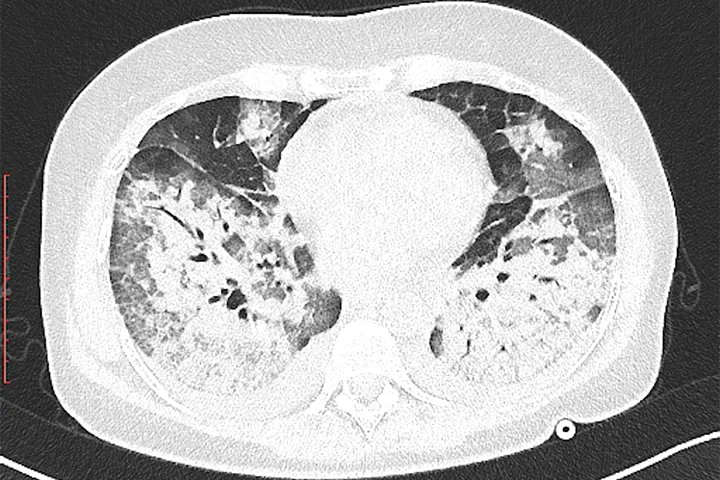

This would be a CT scan of your lungs, as compared to normal ones.